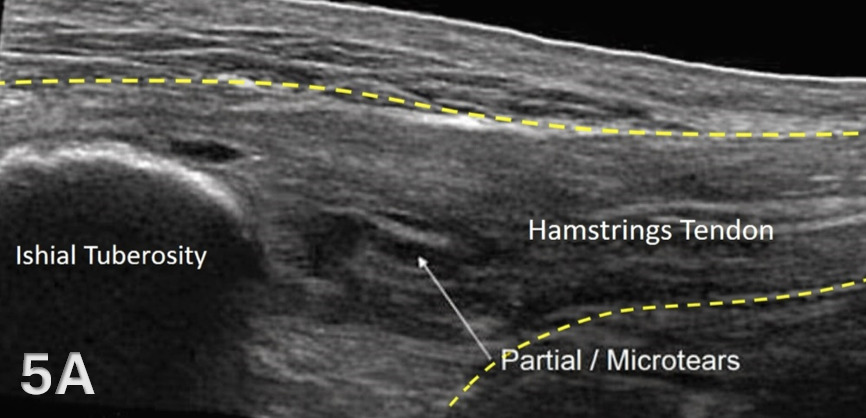

The starting point for examining the proximal hamstring tendon and muscle is at the osseous landmark – the ischial tuberosity.12,13,17–19 The ischial tuberosity can almost always be palpated, giving the examiner a perfect location to begin their scan. The proximal hamstring can be scanned in both the long axis (LAX) and the short axis (SAX). In the LAX view, depending on the probe width and size, one should start proximally to visualize the hyperechoic reflection of the bony cortex of the ischial tuberosity, with its large acoustic shadow underneath. In LAX, the proximal hamstring tendon fibers of the long head of the biceps femoris and the semitendinosus conjoint tendon should be easily seen coming off the attachment of the ischial tuberosity with a clear hyperechoic fibrillar structure running distally from the insertion site on the anterior lateral origin of the ischial tuberosity. The semitendinosus fibers can be easily seen as they reach the ischial tuberosity directly. Lateral to the hamstring muscle complex, the sonographer will see the sciatic nerve that appears as a fascicular, flattened structure that descends between and deep to the long head of the biceps femoris and semimembranosus tendon.1 The probe can be turned 90 degrees for viewing in the SAX. If the probe is moved slightly distally in the SAX view, the biceps femoris will appear as a triangular shape. As the examiner moves distally along the biceps muscle belly, the size will decrease until it appears to disappear. In both views, some toggling may be required to reduce anisotropy.

Pathologic Findings in Lateral Proximal Hamstring Tendon and Muscle Injury

Disruption of fibrillar pattern in partial tears and ruptures. Proximally, it is important to determine if the injury is a free-tendon injury or purely a myotendinous injury.20